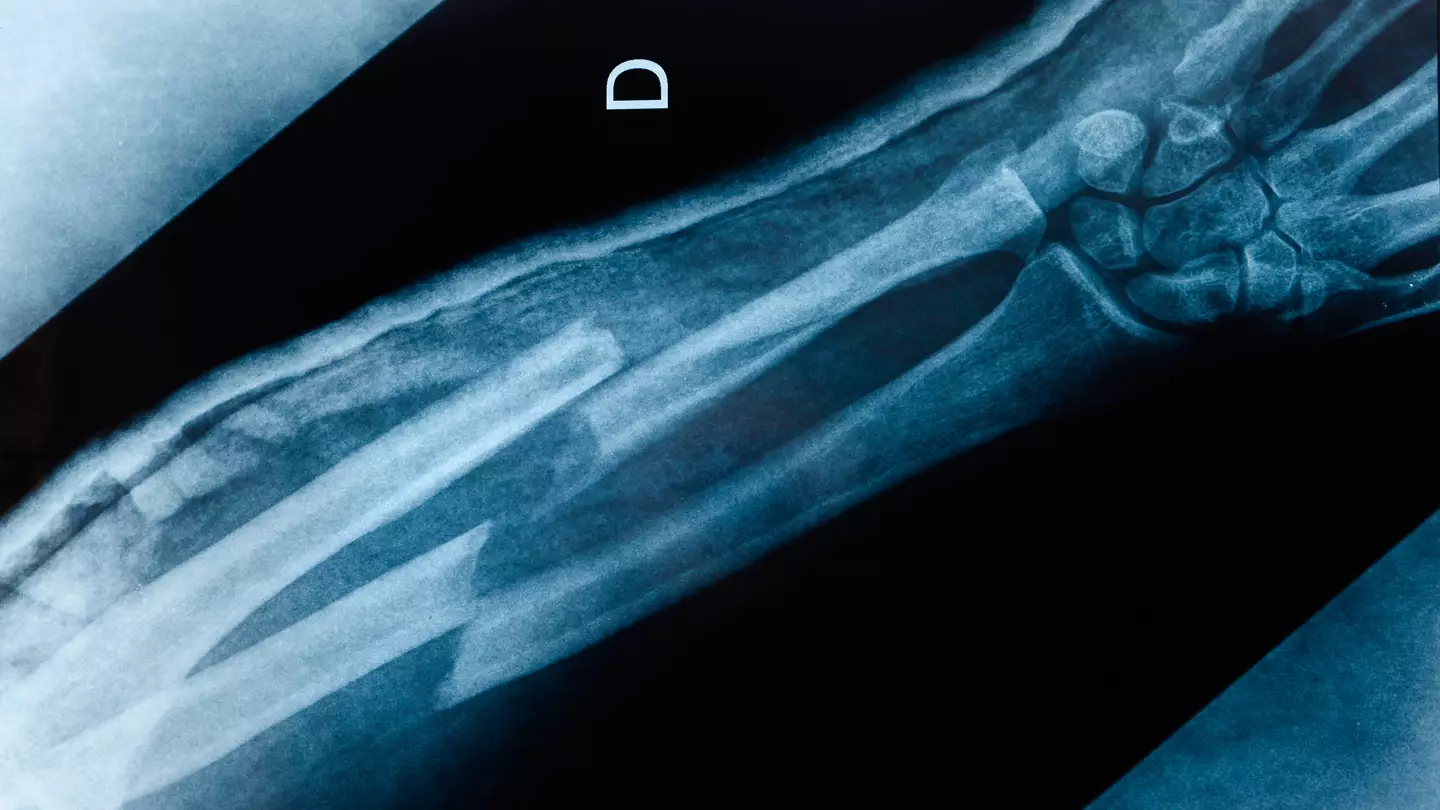

Well, it largely seems to be folks who have come close to breaking a bone - e.g. dislocations, having to have staples, hockey pucks to the face - boasting of how their bones stayed strong. Others ask if they get extra points for breaking other people's bones, while their own skeleton remains unharmed.

And then there are people sharing pictures of themselves in casts, bidding goodbye to the community of no broken bones.